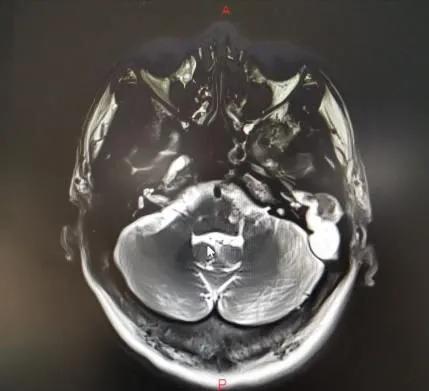

当地医院骨科将武先生诊断为颈椎病,后来又辗转几家医院仍无法确定病因……后来武先生住进郑州市中心医院神经外科,头颅MRI显示:左侧颞叶脑脓肿、中耳乳突炎。原来是因剧烈头痛再发“颅内感染”。

既没有基础疾病,也没有外伤病史,好端端的怎么会反复颅内感染呢?看着武先生的影像片子,神经外科医师突然想到:会不会是中耳炎侵袭到颅内导致的颅内脓肿和感染呢?!随即,该医师迅速联系耳鼻咽喉头颈外科主任李玉杰,详细询问病史、查体和全面查看影像学片子。

李玉杰主任认为,这是一例巨大“中耳胆脂瘤”破坏周围骨质后,蔓延至颅内引发的严重颅内外并发症。病根在中耳,必须尽快手术!